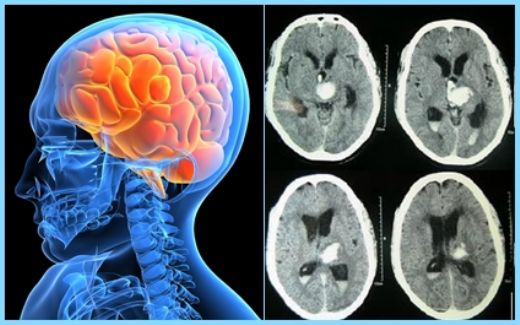

Çocuklarda beyin kanaması, çeşitli nedenlerle meydana gelebilen ciddi bir sağlık sorunudur. Bu durum, çocukların beyin dokusunun zarar görmesine ve yaşamı tehdit eden komplikasyonların ortaya çıkmasına yol açabilir. Beyin kanaması, kafatası içindeki kan damarlarının yırtılması veya sızdırması sonucu meydana gelir ve belirtileri, kanamanın türüne, yerine ve şiddetine bağlı olarak değişiklik gösterir. Beyin Kanaması Türleri Beyin kanamaları, çeşitli tiplere ayrılmaktadır. Bu türler arasında en yaygın olanları şunlardır:

Travmalar, çocuklarda en sık görülen beyin kanaması nedenidir ve bu nedenle çocukların güvenliğini sağlamak oldukça önemlidir. Tedavi Yöntemleri Beyin kanamasının tedavisi, kanamanın türüne, yerine ve çocuğun genel sağlık durumuna bağlı olarak değişiklik göstermektedir. Tedavi yöntemleri şunları içerebilir: